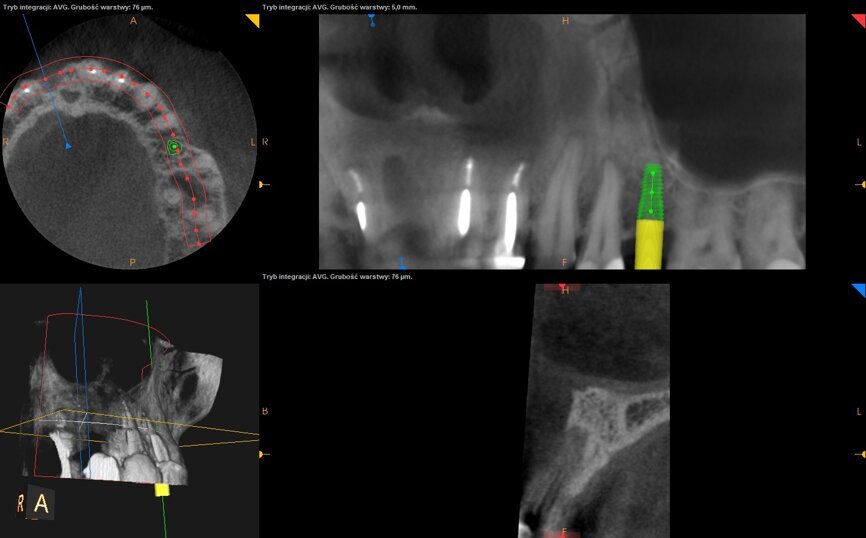

43-letnia pacjentka zgłosiła się do gabinetu w celu uzupełnienia brakującego zęba 11 usuniętego kilka miesięcy temu w innym gabinecie. Brak zostało zaopatrzony czasowym mostem wspartym na zębach 12 i 21. Pacjentka była ogólnie zdrowa. Badanie przedmiotowe wykazało duży zanik kostny przedsionkowo, płytki przedsionek jamy ustnej i niski przyczep wędzidełka wargi górnej (Ryc. 1 i 2). Badanie CBCT wykazało znaczny zanik pionowy wyrostka (Ryc. 3).

Po kolejnych 4 tygodniach wykonano zabieg bocznej regeneracji kostnej wyrostka zębodołowego w okolicy utraconego zęba 11 w przygotowaniu do przyszłej implantacji (Ryc. 9-11). Zastosowano biomodulację przy użyciu głowicy Genova, na rycinie 12 pokazano stan tkanek 3 tygodnie po zabiegu.